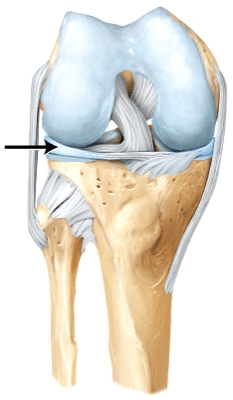

The line is pointing to the _____.